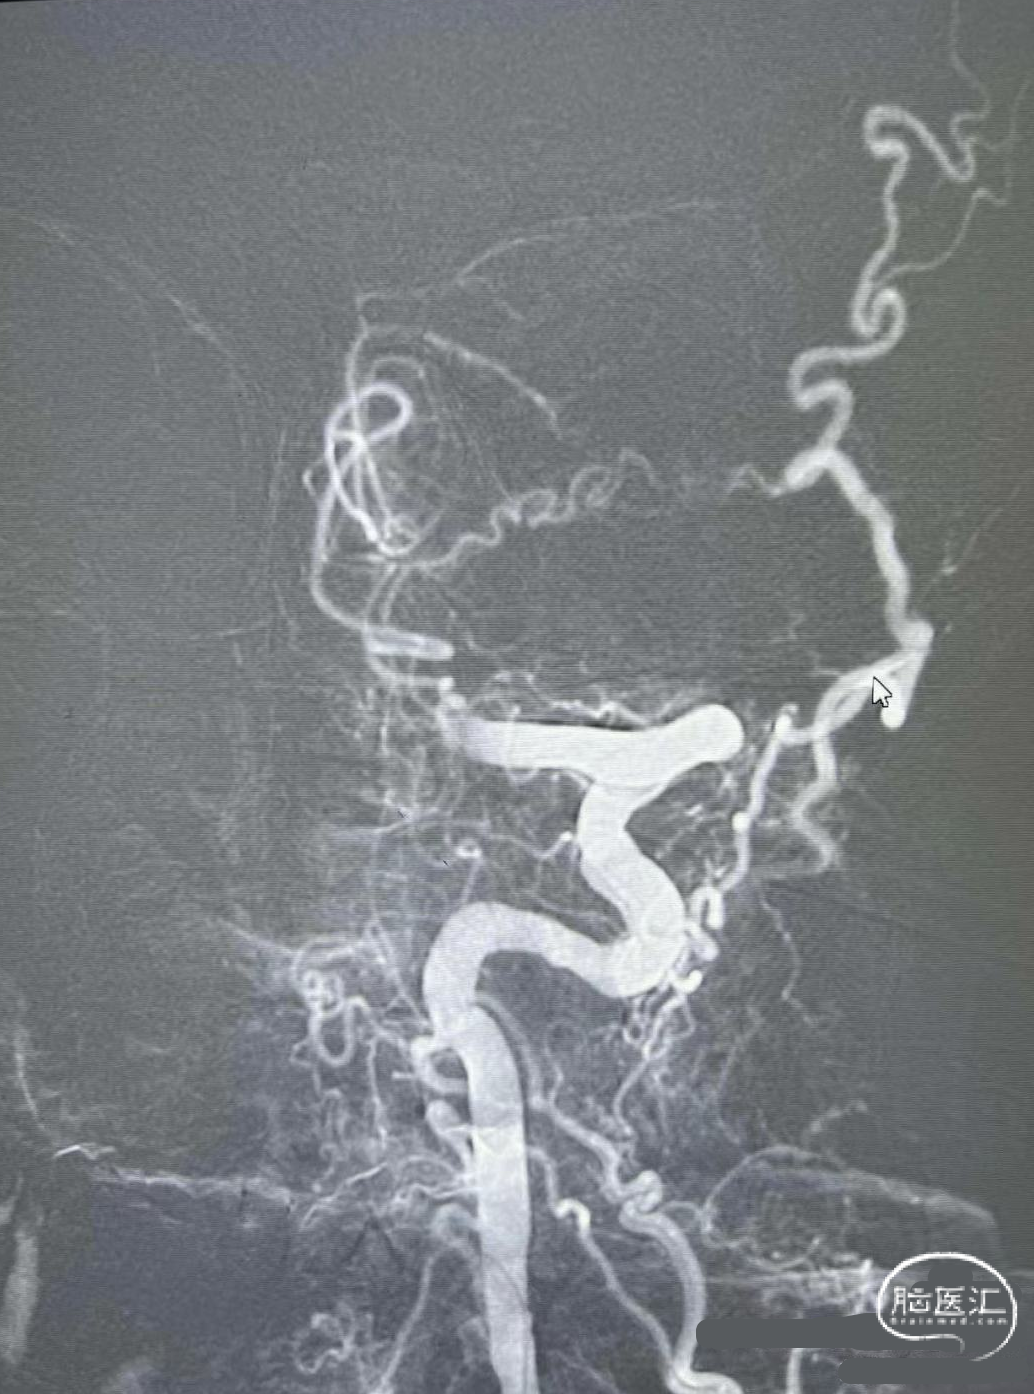

术前DSA影像

右侧颈内动脉起始部中度狭窄,未见血流向后循环代偿。

左侧颈内动脉造影提示后交通开放,代偿供应后循环。

左侧椎动脉开口重度狭窄,前向血流缓慢,V4闭塞。